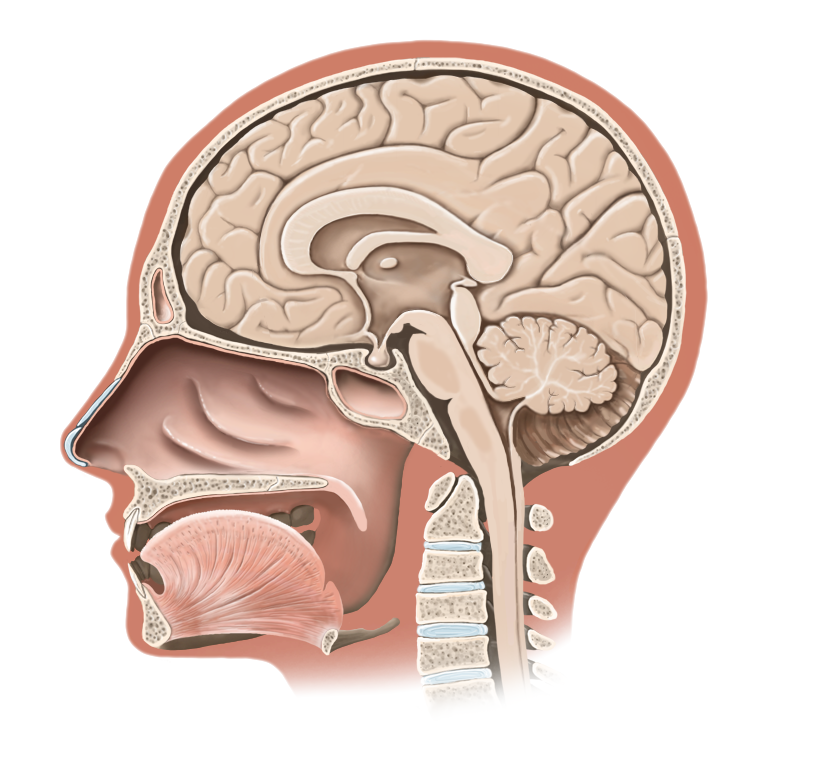

Medical Illustration

All images are works made for hire and are the exclusive property of the client. These are shown as sample purposes of my work only. For licensable work, please see my Illustration Services page.

Medical Illustrator for Precision Graphics, Lachina, and Human Kinetics Publishing (current)

Contract freelancer for many others, some examples of my work below.